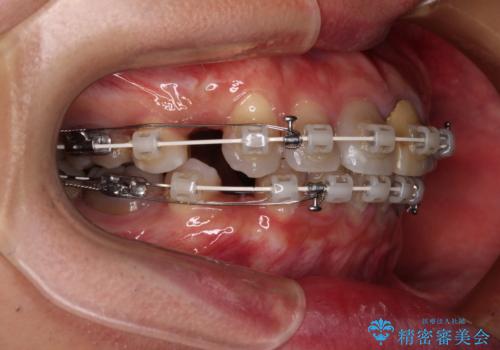

- 矯正装置

- 審美装置

- 飛び出した前歯を気にして来院された患者様です。

口元を引っ込めるために上下左右の第一小臼歯4本を抜歯することとしました。

速やかに治療を進めたいとのことで、表側のワイヤー装置で矯正治療を行うこととしました。